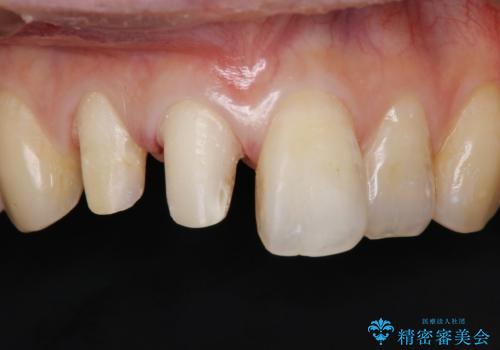

前歯2本の着色が気になる、、、セラミック治療

- 昔治療したプラスチックの材料が目立つから、セラミックで被せたいということを主訴で来院された患者様です。

虫歯治療をし、仮歯を制作し、オールセラミック(スタンダード)にて治療させていただきました。